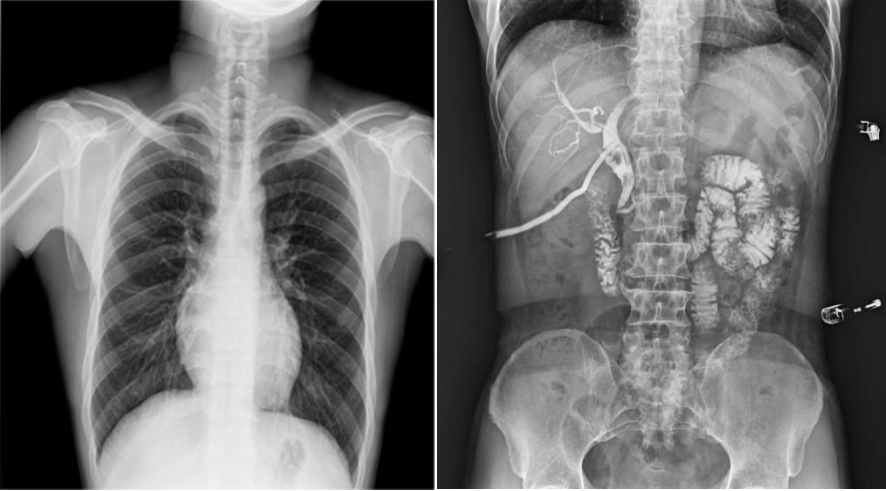

高幀動態(tài)平板,快速獲得高清影像。線性探測平面,圖像無畸變、無失真;17×17英寸超大視野,透視幅面大,一幅畫面即可覆蓋成年人的全胸全腹;30幀/s采集幀速,畫面流暢無卡頓;1800W高清像素點片,影像質(zhì)量攀升新高度;并且能夠在毫秒級時間內(nèi)進(jìn)行動靜態(tài)影像切換,實時點片,快速捕捉病灶部位。